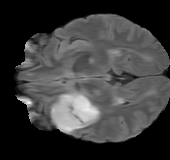

As we observe from the right image in Fig. 2, our BRM, both from MIMO and SISO settings, predicts the performance of dedicated models with a high correlation. We further choose the best three , and perform the last stage of fine-tuning accordingly to (6). A visual evaluation on real data is shown in Fig. 3. For simulated data, please refer to the Supplemental Material section.

Base on the best performing , we perceive that among , , and FLAIR, the results are best when is sampled the most. We suggest that this makes intuitive sense as images provide the best contrast out of the three sequences, which can compensate for the details lost in other images. The same observation can be made on the simulated data, where both and FLAIR show good contrast. When the time setting is changed to non-uniformity, we can see that our search for the best sampling strategy reflects the change. is sampled more as a result of faster acquisition time, while is still sufficiently sampled.

| Sequence | LR | SISO | MIMO | MIMO tuned | GT |

|---|---|---|---|---|---|

(a) 34.38/0.9371

(a) 34.38/0.9371

|

(b) 42.42/0.9883

(b) 42.42/0.9883

|

(c) 44.60/0.9920

(c) 44.60/0.9920

|

(d) 45.50/0.9940

(d) 45.50/0.9940

|

(e) PSNR/SSIM

(e) PSNR/SSIM

|

|

(f) 29.74/0.8903

(f) 29.74/0.8903

|

(g) 36.25/0.9734

(g) 36.25/0.9734

|

(h) 36.42/0.9752

(h) 36.42/0.9752

|

(i) 37.70/0.9832

(i) 37.70/0.9832

|

(j) PSNR/SSIM

(j) PSNR/SSIM

|

|

(k) 39.89/0.9311

(k) 39.89/0.9311

|

(l) 43.94/0.9864

(l) 43.94/0.9864

|

(m) 44.74/0.9883

(m) 44.74/0.9883

|

(n) 45.49/0.9894

(n) 45.49/0.9894

|

(o) PSNR/SSIM

(o) PSNR/SSIM

|